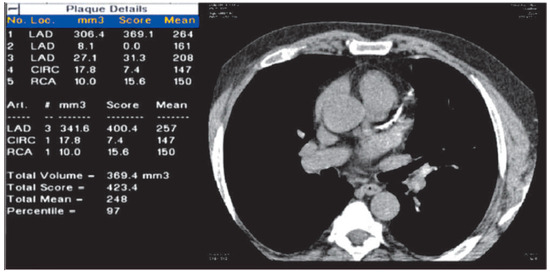

Coronary Risk Assessment by Computed Tomography in Asymptomatic Individuals

by Michel Romanens, Roberto Corti, Michèle Depairon, Roger Darioli, Beat Kaufmann, Nicolas Rodondi, Marco Roffi and Georg Noll

Cardiovasc. Med. 2013, 16(5), 144; https://doi.org/10.4414/cvm.2013.00153 - 22 May 2013

Coronary risk prediction remains a difficult task: coronary risk charts rely on major independent coronary risk factors, which do not necessarily predict risk in different populations, are poorly validated externally and may need recalibration to improve predictive accuracy. Coronary artery calcification (CAC) can be visualised and quantified using computed tomography. On the basis of receiver operating characteristic (ROC) curves, several studies have shown that CAC does confer incremental value on coronary risk charts and increase the accuracy of outcome prediction. CAC measurements may be considered in intermediate- risk subjects, or in those where traditional cardiovascular risk factors fail to assess risk adequately, for example, subjects with a family history of premature coronary artery disease. Computed tomography coronary angiography (CTCA) visualises and helps to quantify soft coronary plaques and stenosis. CTCA in asymptomatic patients has very rarely been studied and its diagnostic accuracy in comparison with invasive procedures is acceptable in noncalcified coronary segments. There being no current role for CTCA imaging for asymptomatic patients to reduce risk in primary care, CTCA should not be used to stratify coronary risk. Full article